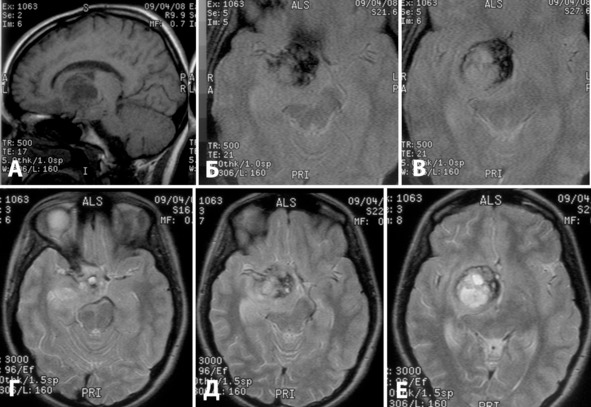

Из анамнеза известно, что в течение нескольких лет пациентку беспокоили головные боли. В октябре 2006 года эпизод сильной головной боли, выраженной общей слабости с подъемом АД до 150/90 (клиническое САК). Осмотрена бригадой скорой помощи, не госпитализирована. В течение недели симптоматика регрессировала. Ухудшение состояния 28.10.2007, когда у больной вновь внезапно появилась головная боль, произошла потеря сознания. Бригадой скорой помощи доставлена в детскую городскую клиническую больницу. Согласно данным медицинского осмотра при поступлении уровень сознания был на уровне глубокого оглушения, выявлялась менингеальная симптоматика, анизокория за D> S, отсутствие фотореакции OD, левосторонний глубокий гемипарез. При КТ от 28.10.2007 выявлено САПК с гематомой в базальных отделах правой лобной и височной долей, гипоталамической области, кровь в латеральной щели, субарахноидальных пространствах справа, смещение срединных структур на 6 мм (рисунок 10: А, Б). Больная переведена в НИИ Нейрохирургии. При поступлении на фоне выраженной общемозговой симптоматики и снижения уровня бодрствования (умеренное оглушение) выявлялся парез III нерва справа, центральный парез VII нерва слева, умеренный левосторонний пирамидный гемипарез. Имелась мягкая орально-стволовая симптоматика. При ТК УЗДГ выявлено умеренное ускорение кровотока по правой СМА. На тотальной ангиографии от 01.11.2007 данных за сосудистую патологию не выявлено (рисунок 10: В, Г). За время пребывания в институте отмечалась значительная положительная динамика в неврологическом статусе. Сохранялись парез III нерва справа, центральный парез VII нерва слева, легкая левосторонняя пирамидная симптоматика. По данным КТ от 31.10.2007 объем гематомы в подкорковых структурах справа и в базальных отделах мозга оставался прежним, сохранялось смещение срединных структур и сдавление желудочковой системы. По данным ультразвукового обследования отмечался регресс вазоспазма. Для продолжения лечения переведена в стационар по месту жительства. Рекомендована повторная АГ через 3—4 месяца.

При повторной госпитализации в НИИ Нейрохирургии в неврологическом статусе сохранялись легкая дисфункция III и VII нервов, небольшое сужение полей зрения по типу левосторонней гомонимной гемианопсии. При повторной ангиографии данных за патологическую сосудистую сеть не выявлено. Больной выполнена МРТ, при которой выявлена кавернома в гипоталамической области и подкорковых узлах справа (рисунок 11). В связи с минимальной неврологической симптоматикой и высоким риском тяжелого неврологического дефицита решено продолжить наблюдение. Рекомендовано МРТ через год.

Рисунок 10. КТ в аксиальной проекции на 4-й день после кровоизлияния (А, Б) и правосторонняя каротидная АГ в прямой и боковой проекции (В, Г). На КТ выявляется гематома в базальных отделах лобной и височной долей, гипоталамической области, кровь в цистернах основания и правой латеральной щели. На АГ данных за патологическую сосудистую сеть не выявлено.

Рисунок 11. МРТ через 5 мес после кровоизлияния в режимах Т1 (А), Т2* (Б, В) и Т2 (Г, Д, Е). А – сагиттальная проекция, Б, В, Г, Д, Е – аксиальная проекция. Выявляется кавернома Ia типа, расположенная в заднелобно-гипоталамической области и подкорковых ядрах справа.